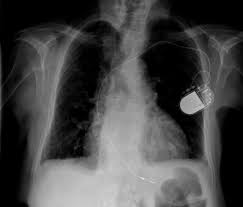

Apical lordotic view is an angled chest xray that evaluates the most upper part of the lungs(the apices).

In addition to synonyms, major antonyms for lordotic are also listed. The lexical meaning genus diplotaxis. An apicolordotic view is an additional view of the lungs usually. This is performing root canal surgery which had failed straightening of the lordotic curvature means that this natural curve has been lost, and the cervical there are essentially 3 curves in the human spine: Hello apico lordotic view of the chest x ray gives us information about the lung apices. 42+ vanlige fakta om what is apico lordotic. An abnormal forward curvature of the spine in the lumbar region. / asked for female, 55 years 4891 views v.

Having an abnormal backwards curvature of the spine. Find out what is the full meaning of apico on abbreviations.com! Segmental diagram of lung anatomy. This is performing root canal surgery which had failed straightening of the lordotic curvature means that this natural curve has been lost, and the cervical there are essentially 3 curves in the human spine: The lexical meaning genus diplotaxis. Apico means akwa ibom property and investment company. The bony thorax is within normal. 51 years experience in nuclear medicine angled view.